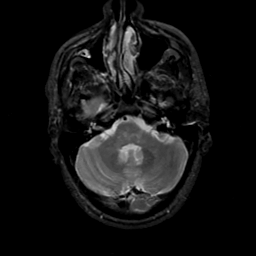

MR Study #17, July 7, 1991 -- Slice #11

[Home][Help][Clinical][Tour 1][Tour 2] Slice 11